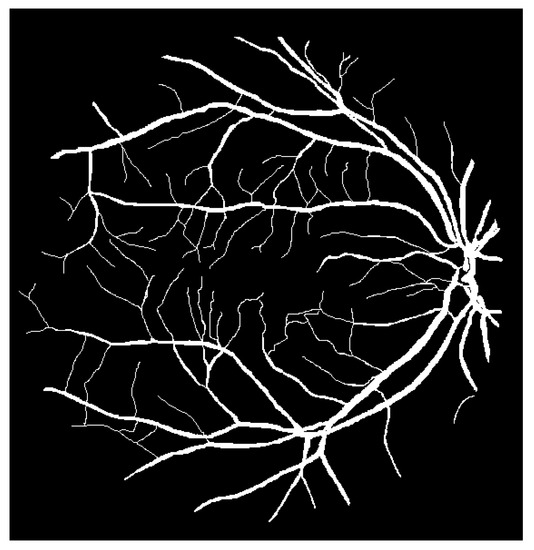

The techniques that are often used for automating retinal vessel segmentation are based on machine learning [28,29,30,31,32,33,34,35,36,37,38,39,40,41,42,43,44,45,46]. This is because replacing the lost vessel portion of an original retina image with another person’s vessels lacks ethical credibility. On the other hand, machine learning is credible because it learns patterns in which people’s vessels are spread. The focus of most recent studies is on deep learning-based supervised learning, and this is the same for retinal vessel segmentation automation. To learn vessel images, masks must be prepared in advance for the vessel portion. Figure 4 shows the manually prepared vessel portion of Figure 2. Moreover, the areas of the vessels must be specified when the dataset’s retina images are in a different environment (minor changes in position that occur when the image is captured). Figure 5 shows the position mask for Figure 2.

Figure 4. Retinal vessels of Figure 2.